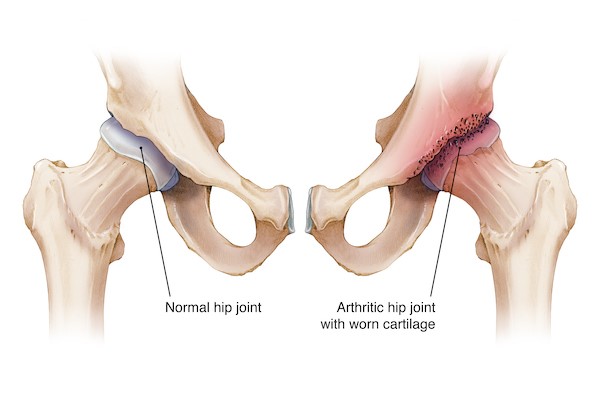

Hip arthritis can be extremely debilitating. Patients often feel pain around the upper thigh but mostly in the groin (yes, that’s where a hip joint is!) Other classical symptoms are difficulty in putting on shoes and socks, getting in and out of a car, limping and pain during intimacy.

It involves removing the worn hip joint and replacing it with metal implants in the socket (Pelvis) and thigh (Femur) bones. I will show you the actual implants which I recommend once I have assessed you. You might be surprised to note that they are not connected to each other! It does need a reasonable amount of skill from your surgeon to achieve a good balance between movement and stability of hip joint. The operation takes approximately 60-90 minutes to complete and your expected length of stay in hospital is between 2-3 days – but many of my patients are ready to go home the next day or sometimes on the same day, i.e., ‘Day-Case’ hip replacement!